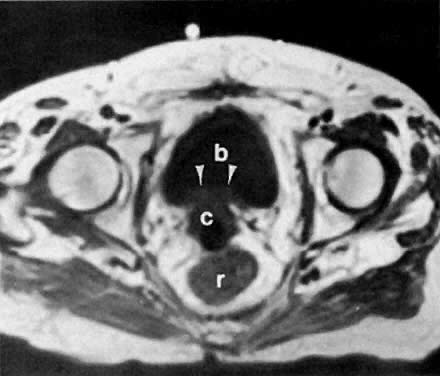

Fig. 5. Cervical carcinoma stage IB. CT scan of the pelvis ( A) shows a well-marginated posterior cervical mass stretching the cervical canal anteriorly. Transverse ( B) and sagittal ( C) sonograms of the pelvis show a large, well-defined, inhomogeneous, solid posterior cervical mass stretching the cervical canal anteriorly. It appears confined to the cervix without parametrial spread. The relationship of the mass to the vagina, uterus, rectum, and bladder is best demonstrated on the sagittal view. ( c, cervical mass; e, cervical canal; v, vagina; u, uterus; r, rectum; b, bladder.)

In locally confined disease, a cervical mass may be seen by ultrasound (Fig. 5B and C). In locally advanced disease, the cervix may become diffusely enlarged, inhomogeneous, and irregularly marginated (Fig. 6A and B).

Fig. 6. Advanced cervical carcinoma. Sagittal ( A) and transverse ( B) sonograms of the pelvis show a markedly enlarged, irregular cervical mass invading both parametria ( black arrows ), encasing the right ureter laterally, and obliterating the fat planes ( white arrows) between the cervix and bladder anteriorly, and cervix and rectum posteriorly. The mass is obstructing the uterus, causing hydrometras. Sagittal sonogram ( C) of the right kidney shows moderate hydronephrosis. ( c, cervical mass; ur, ureter; b, bladder; h, hydrometras; k, kidney.)

The presence of hydrometras should raise the suspicion of cervical or endometrial carcinoma. It is best demonstrated by ultrasound (see Fig. 6A), but can be seen by both MRI (Fig. 7) and CT (Fig. 8).11,12 This finding, however, is nonspecific because it can also be seen in benign cervical strictures caused by either previous cervical inflammation (Fig. 9) or pelvic irradiation (Fig. 10).

Fig. 7. T2-weighted sagittal MRI of the pelvis shows cervical carcinoma ( c) causing hydrometras ( h ).

Fig. 8. Axial CT scan of the pelvis in a 55-year-old woman with stage IB cervical carcinoma causing obstruction of the uterus ( u ). ( b, bladder; arrows, uterus; r, rectum.)

Fig. 9. Sagittal scan of the uterus ( u) shows hydrometras. Cervix ( c) is normal in size. Patient had no known cervical or endometrial cancer.

Fig. 10. Sagittal T2-weighted MRI of the pelvis shows moderate hydrometras ( h) caused by postirradiation cervical scarring.